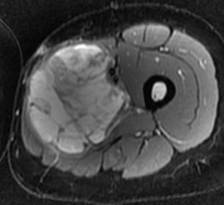

Histiocytofibrome malin. Noter l’aspect hétérogène en T2, avec prise de contraste hétérogène

Histiocytofibrome malin